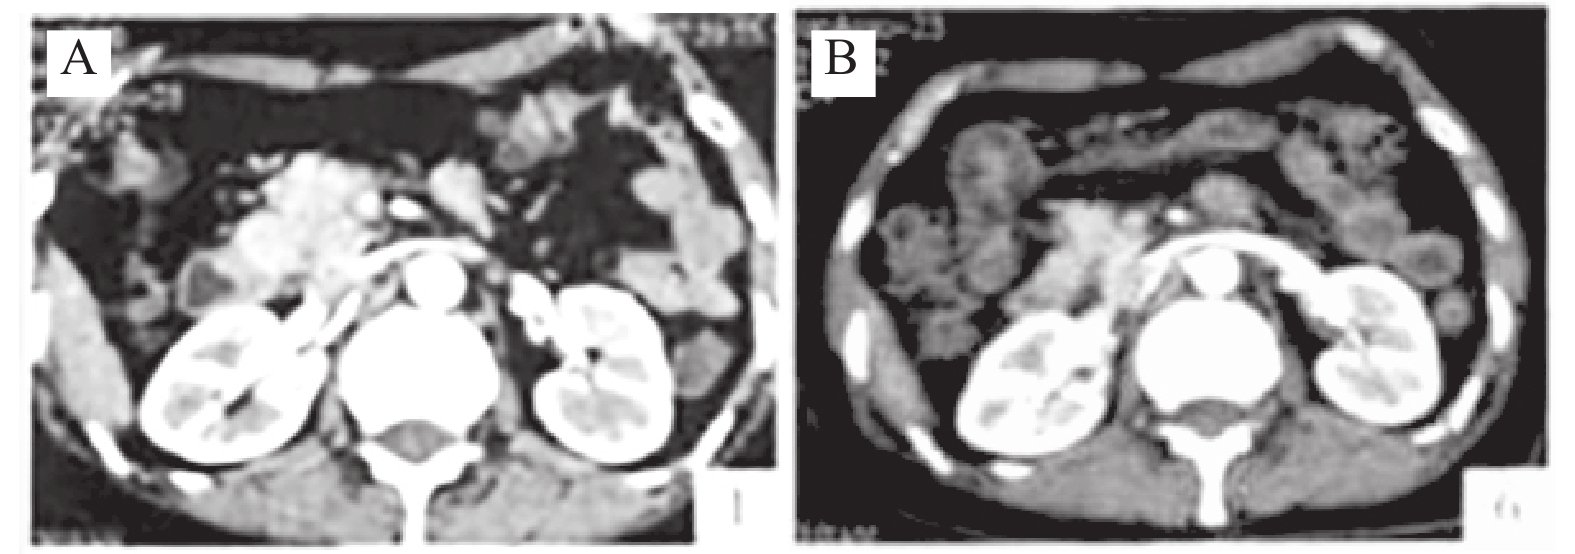

线粒体途径铁死亡在尿毒症毒素相关的心肌损伤中的作用及机制

周亚萍, 邸芳芳, 王伟

摘要(280) HTML(165) PDF (103)

摘要:

目的  探讨尿毒症毒素硫酸吲哚酚(indoxyl sulfate,IS)在慢性肾病(chronic kidney disease,CKD)大鼠心肌损伤中的作用及其通过线粒体途径介导铁死亡的机制。  方法  采用5/6肾切除法建立CKD模型,将大鼠随机分为假手术组、CKD组、IS组、CKD+IS组及CKD+IS+铁死亡抑制剂Ferrostatin-1(Fer-1)组。通过比色法检测心肌组织超氧化物歧化酶(superoxide dismutase,SOD)活性、丙二醛(malonaldehyde,MDA)、还原型谷胱甘肽(reduced glutathione hormone,GSH)及Fe2+含量;采用二氢乙啶(dihydropyridine,DHE)荧光法观察活性氧(reactive oxygen,ROS)水平;RT-qPCR与Western blot检测铁死亡相关基因长链脂肪酸-CoA合成酶4(acyl-coA synthetase long-chain family member 4,ACSL4)、胱氨酸/谷氨酸逆转运蛋白(solute carrier family 7 member 11,SLC7A11)和GPX4的mRNA及蛋白表达;TUNEL法评估心肌细胞凋亡;同时检测线粒体ATP含量并通过透射电镜观察其超微结构变化。  结果  与假手术组相比,CKD组大鼠体重下降,心脏质量增加(P < 0.05),SOD与GSH水平下降,MDA、Fe2+及ROS显著升高(P < 0.05);ACSL4表达上调,而SLC7A11与GPX4显著下调(P < 0.05),并伴随大量心肌细胞凋亡及ATP含量减少(P < 0.05)。慢性IS暴露进一步加剧上述变化(P < 0.05),表现为线粒体肿胀、嵴断裂及膜密度增加等典型铁死亡超微结构特征;而Fer-1干预可逆转这些损伤,使ATP水平恢复、线粒体形态改善。  结论   IS可通过激活线粒体途径诱导铁死亡,加重CKD大鼠心肌氧化应激与能量代谢障碍,从而促进心肌细胞凋亡;Fer-1干预可显著缓解IS诱导的线粒体损伤与心肌铁死亡。